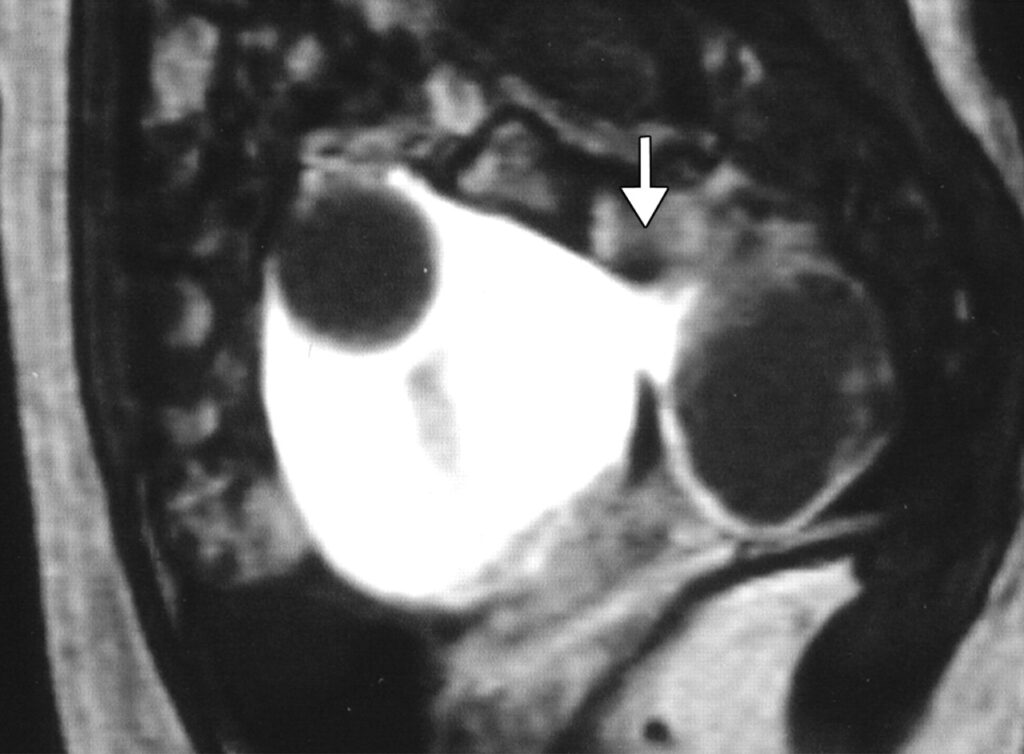

- UFE has a success rate of 90%, providing relief from fibroid symptoms like heavy menstrual bleeding, pelvic pain, and increased urinary frequency (Fig. 2)